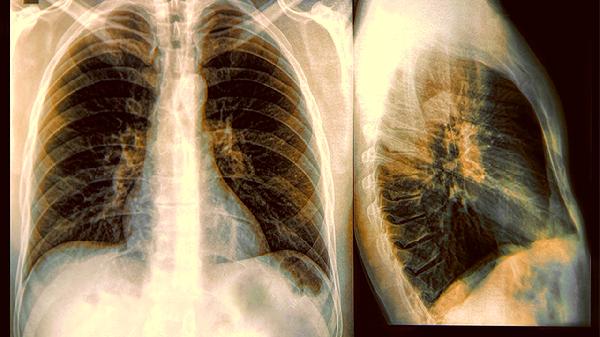

2.篩查誤區

常規體檢中的胸片檢查對早期病變的識別率不足20%,就像用漁網撈蝦米。更值得注意的是,近40%的肺部腫瘤生長在胸片盲區,這個數據揭示了傳統檢查手段的局限性。

1.低劑量螺旋CT的價值

這項檢查的輻射量相當於乘坐4小時飛機,卻能發現小至2毫米的結節。相比胸片檢查,它能將早期肺癌檢出率提升至90%以上,就像給肺部裝上了高清顯微鏡。